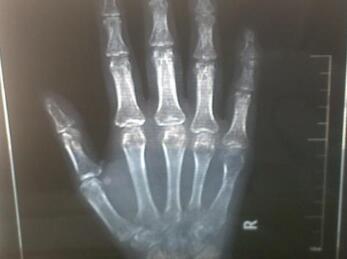

林女士来到我院的时候,手指关节已经明显肿大,随即,杜爱华主任就为林女士做了详细的体查,症状:四肢关节肿大疼痛,不能穿衣梳头,行走艰难,变天时更严重。

图:林女士比较严重的手指关节检查图

在接受过查体之后,杜爱华主任又安排了林女士去接受风湿病的全面的检查,杜爱华主任又为她详细的分析了她的情况。化验:测体温37.8℃,类风湿因子阳性·血沉112mm/h。X线示:Ⅳ期改变。舌质暗,舌体胖大,苔黄厚腻,脉沉细。